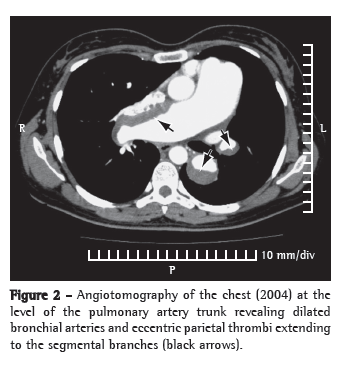

In April of 2004, the patient presented progressive functional worsening, reaching functional class IV. Angiotomography of the chest revealed eccentric parietal thrombi, predominantly in the pulmonary artery trunk (from the main branches to the subsegmental branches, bilaterally), with calcifications peripheral to the thrombi (Figure 2). There was also mosaic perfusion in the pulmonary parenchyma, together with bronchial artery dilatation. Tests for deep vein thrombosis and thrombophilia were negative. Despite the functional class worsening, the distance covered on the six-minute walk test (6MWT)-used to assess functional capacity-was 414 m, a dissociation that has previously been described in patients with IPAH.(7) The patient remained adequately anticoagulated throughout the treatment period. The tomographic images were fully consistent with the diagnosis of CTEPH. Fortunately, our knowledge of the previous diagnosis (IPAH) allowed us to opt for clinical treatment with 75 mg/day of sildenafil.